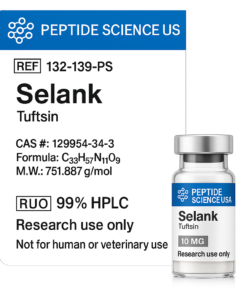

Related products

Peptides

Peptides

Peptides

Peptides

Peptides

Peptides

Peptides

Peptide